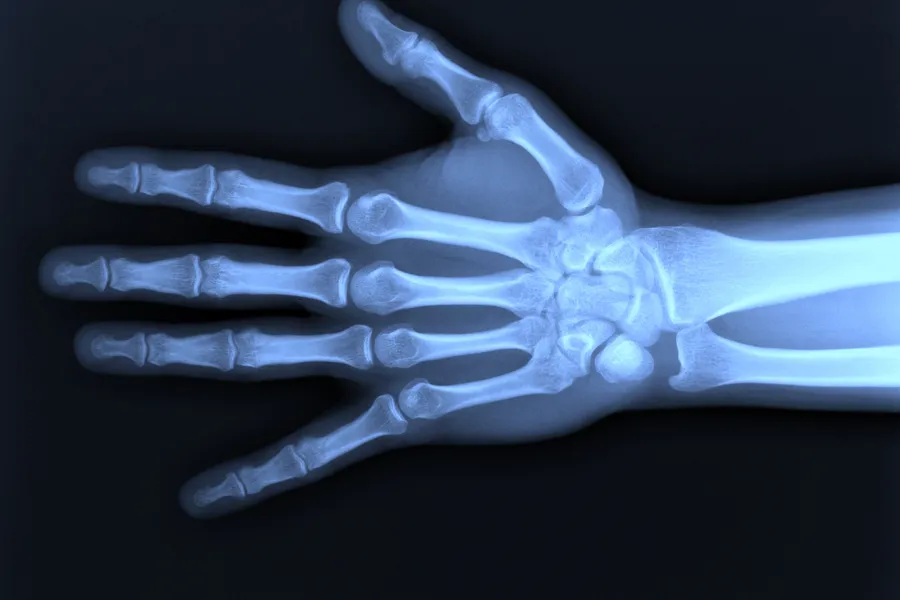

Gradering av håndskjelett

Den andre metoden som brukes i BioAlder-verktøyet er gradering av modningen i håndskjelett/håndrot. Her brukes et rammeverk kalt Greulich & Pyle-atlaset som ble utarbeidet i Ohio, USA på 1930-tallet.

Under graderingen av håndrøntgen som brukes i BioAlder vurderer radiologen hvilket av skjelettstadiene som ligner mest på røntgenbildet til den som skal aldersfastsettes. Skjelettstadiumet vurderes av to ulike radiologer og det endelige stadiet settes inn i modellen. BioAlder tar den vurderte skjelettalderen/skjelettstadiet fra Greulich & Pyle-atlaset og knytter dette opp til et stort datamateriale for å kunne anslå et aldersintervall.